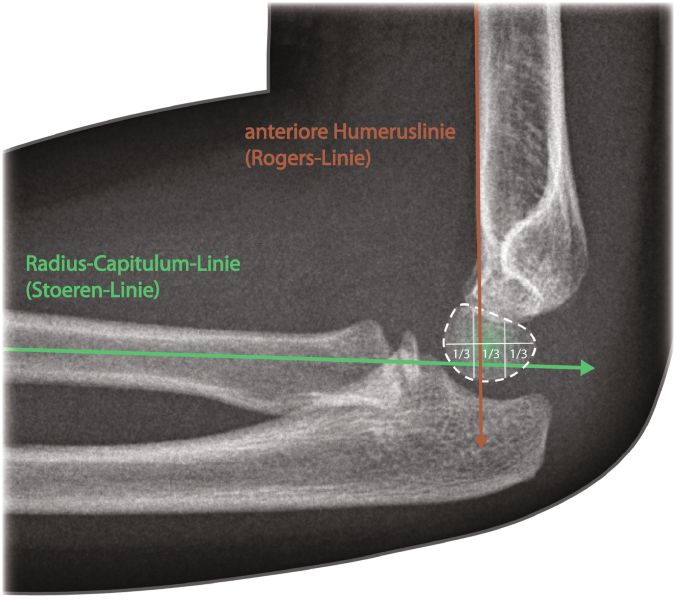

Radiologische Hilfslinien

Vordere Humeruslinie (Rogers Linie)

- Läuft normalerweise durch das mittlere Drittel des Capitulum humeri

- Bei suprakondylären Humerusfrakturen häufiger Dislokation des Capitulum nach dorsal - Vordere Humeruslinie schneidet im ventralen Drittel des Capitulum

Radiocapitellare Linie (Stoeren Linie)

- Hilfslinie, die als Verlängerung des Radiusschaftes durch das Capitulum verläuft

- Hinweis auf Radiuskopfluxation wenn die Linie nicht durch das Capitulum läuft